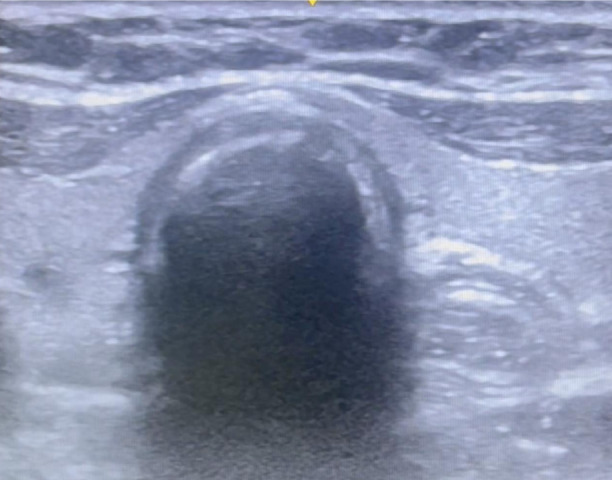

目的:气管插管成功是先进气道管理的关键步骤。气管插管成功的金标准是潮末二氧化碳(etCO2)监测,尽管最近的研究表明超声波也可以使用。在本研究中,我们通过比较超声和etCO2监测,探讨了气管插管成功的时间敏感性早期识别。方法:本研究纳入了104例在全麻下需要气管插管的择期手术患者。将取下面罩到超声显示气管颤振的时间与气管插管后连续6次超声波形的出现时间进行比较。结果:超声识别气管插管成功的时间为(21.63±7.38)秒,比超声检查(40.62±7.93)秒更快。结论:eCO2需要6次连续波形时间才能确认插管成功,且存在假阳性率。在不需要正压通气的低肺血流量患者中,如在心肺复苏期间,在创伤等高风险紧急插管中,或在可以实时确认插管的困难气道中,用超声补充金标准etCO2更快、更可靠。超声是一个可靠的和更快的工具,早期识别成功的气管插管比末潮二氧化碳。

Methods: The study included 104 patients who were posted for elective surgery under general anaesthesia requiring endotracheal intubation. The time from removal of the face mask to ultrasound visualization of flutter in the trachea was compared with that of the appearance of six consecutive capnography waveforms following endotracheal intubation.